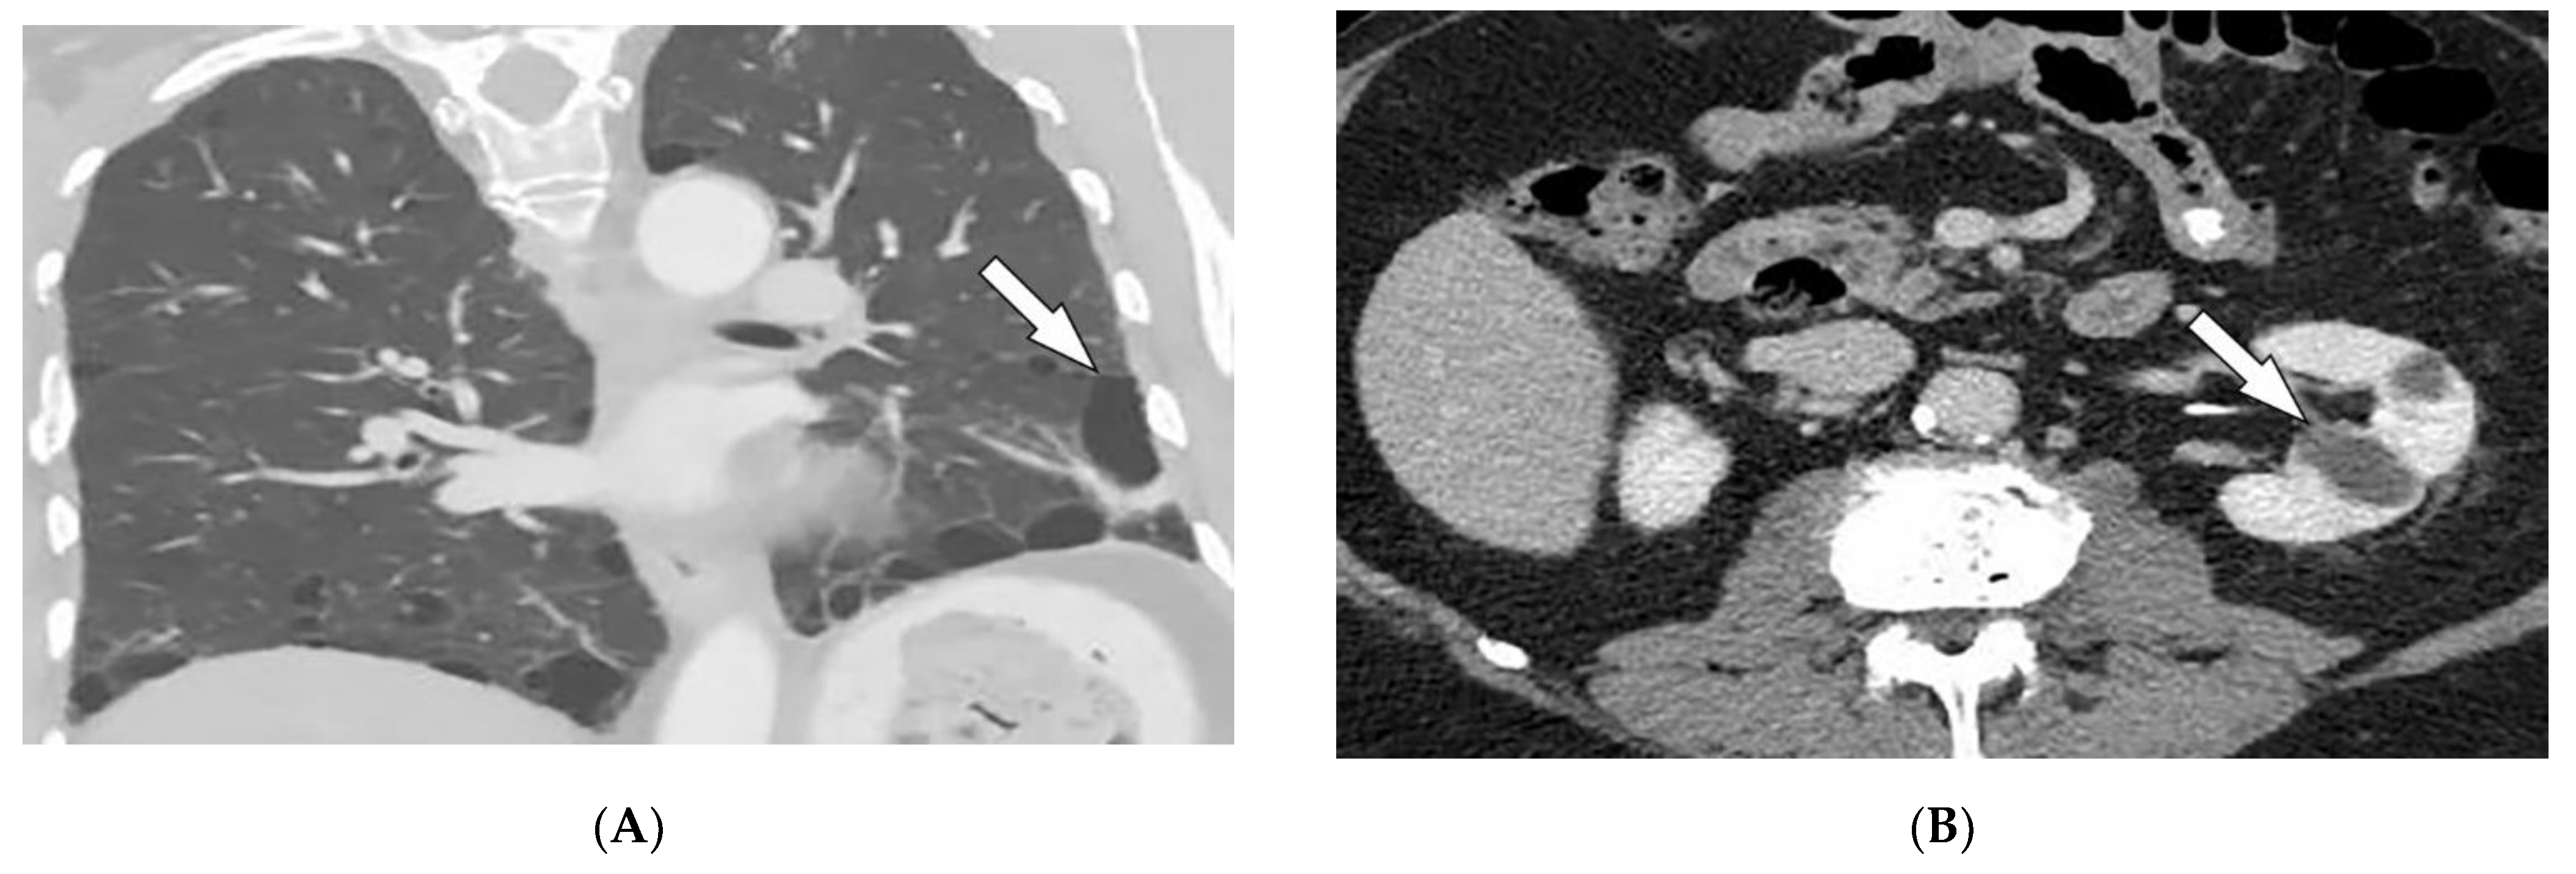

| Granulomatosis with polyangiitis (Wegner’s) | Palpable purpura Subcutaneous nodules Pyoderma-gangrenosum-like ulcerations Lung lesions and hemoptysis Glomerulonephritis Peripheral neuropathy, mononeuritis multiplex Chronic sinusitis and saddle nose deformity | Bilateral cavitary lung lesions with a ground-glass halo sign Mucosal thickening Nasal septal perforation Hyperostosis |

| Polyarteritis nodosa | Palpable purpura Painful nodules on lower legs Livedo reticularis Medium-sized artery vasculitis | Microaneurysms and constrictions of medium-sized arteritis (beaded appearance) |